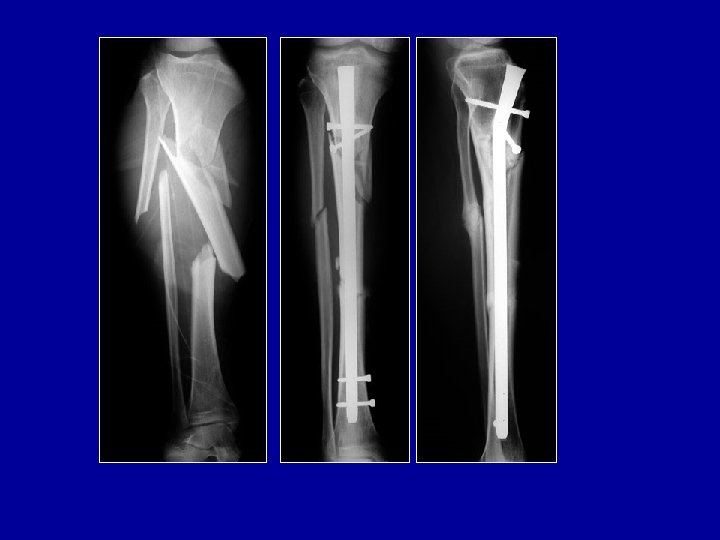

Enclouage à foyer fermé du tibia • • • Installation pour enclouage du tibia Table orthopédique Traction longitudinale Broche trans-calcanéenne ou étrier de Cunéo Genou fléchi Contrôle radioscopique de la réduction

Installation pour enclouage du tibia • Le canal médullaire est abordé en avant des épines tibiales • Introduction du guide puis des alésoires et enfin du clou

Clou pour tibia Courbure adaptée Clou creux

Enclouage du tibia à foyer fermé Clou simple Clou à ailettes Clou verrouillé par vis

Qualité du cal osseux après enclouage du tibia à foyer fermé Avantages de l’enclouage Préservation de l’hématome Pas de dépériostage Cal volumineux

Clou de tibia Verrouillage proximal Verrouillage distal Photo J. Chouteau

Clou à foyer fermé verrouillé Vis enlevées à 3 mois Guérison 6 mois